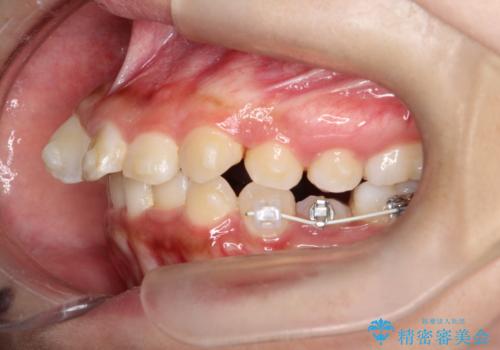

- 歯のデコボコ(叢生)を気にされて来院されました。精密な検査の結果、中等度の叢生と診断。患者様のご希望に合わせ、透明で目立ちにくい**インビザライン(マウスピース矯正)**による治療計画を立案しました。歯を抜かずに、歯列弓(歯が並ぶアーチ)を少しずつ拡大することで、歯が並ぶスペースを確保し、叢生を改善することを目指します。

今回の矯正治療では、透明なマウスピース型の装置インビザラインを使用しました。この装置は目立ちにくく、取り外しが可能なため、食事や歯磨きも普段通りに行えます。治療は、緻密に計算された治療計画に基づき、段階的に作製されたマウスピースを交換していくことで、歯列弓全体を徐々に広げていきました。この歯列弓の拡大により、不足していたスペースを確保し、歯のデコボコを効果的に解消。抜歯することなく、整った美しい歯並びと良好な咬み合わせを獲得していただけました。